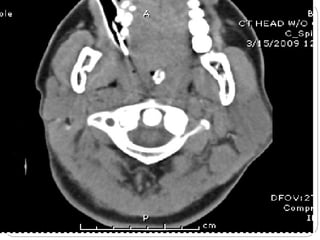

Computed Tomography (CT)

1. Also called CAT scanning or “CT”

2. X-Ray beam moves 360 around the patient

3. Consecutive x-ray “slices” around the patient

4. Computer can recreate 3D image of the body or

Image “slices” reconstructed by computation

5. Best for evaluating bone and soft tissue tumors,

fractures, intra-articular abnormalities, and

bone mineral analysis

Computed Tomography

6. The image formed is related to the subjects

density

7. Image display on computer or multiple films

8. New technology is multislice helical scanner

CT (by Picker)

• #52 What color is air on an a X-ray or CT? where is the problem? CT of mesothelioma